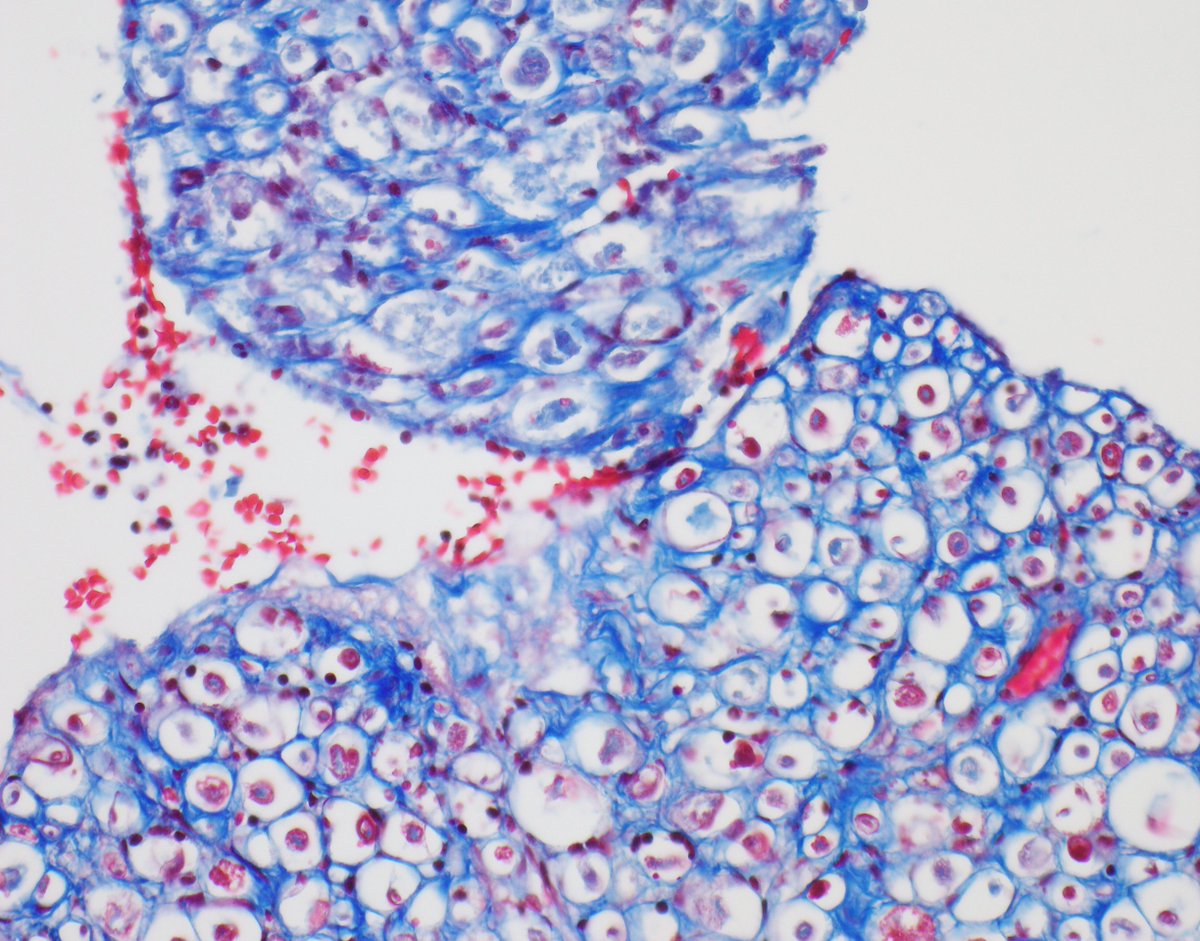

Nice example of a clear cell meningioma with the characteristic "blocky" collagen and absence of SMARCE1 expression.